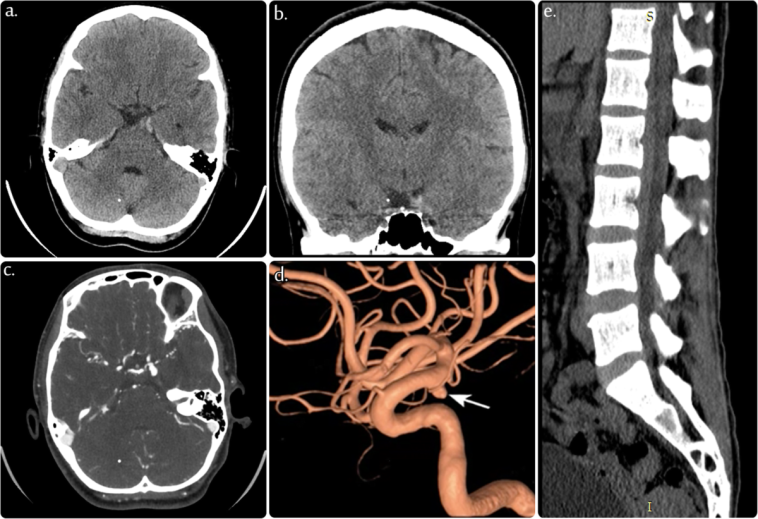

Originally Post From https://www.cureus.com/articles/407074-a-fatal-case-of-a-ruptured-posterior-communicating-artery-aneurysm-in-a-patient-with-undiagnosed-klippel-feil-syndrome